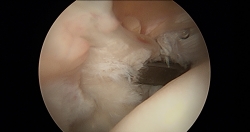

El primer paso que seguimos para la sutura del tendón del subescapular es la identificación de la lesión (Figura 3). En las roturas parciales, es relativamente sencillo identificarlas; las crónicas pueden ser más laboriosas por la retracción y fibrosis del tendón. El signo de la coma nos ayuda a identificarla(2). Realizamos el portal anterior y colocamos una cánula. El examen artroscópico de la articulación ayuda a identificar las lesiones asociadas.

Figura 3. Rotura completa del tendón del subescapular. Paciente en silla de playa, hombro derecho, visión desde el portal posterior con óptica de 30°. Tracción del tendón.